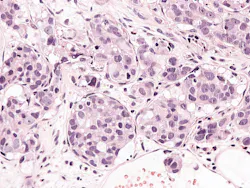

The study involved 1523 patients with high-risk or metastatic prostate cancer who were randomized to standard-of-care treatment with androgen deprivation therapy (ADT) or to chemotherapy plus ADT. Patients were then followed for a median of 14 years. Among the 832 patients with metastatic prostate cancer, those with higher Decipher Prostate scores had improved survival benefit (HR 0.64, 95% CI 0.48-0.86) from docetaxel, while those with lower Decipher scores did not (HR 0.96, 95% CI 0.71-1.30; biomarker-treatment interaction p=0.039).

For the current study, Veracyte performed whole-transcriptome analysis of all prostate samples. In addition to the commercially available Decipher Prostate test, other research-use-only gene signatures were evaluated. One notable finding was that metastatic tumors with both a high Decipher Prostate test score and a PTEN-inactive gene signature had the greatest benefit from the addition of docetaxel, suggesting potential opportunities to enable further-personalized patient care in the future.